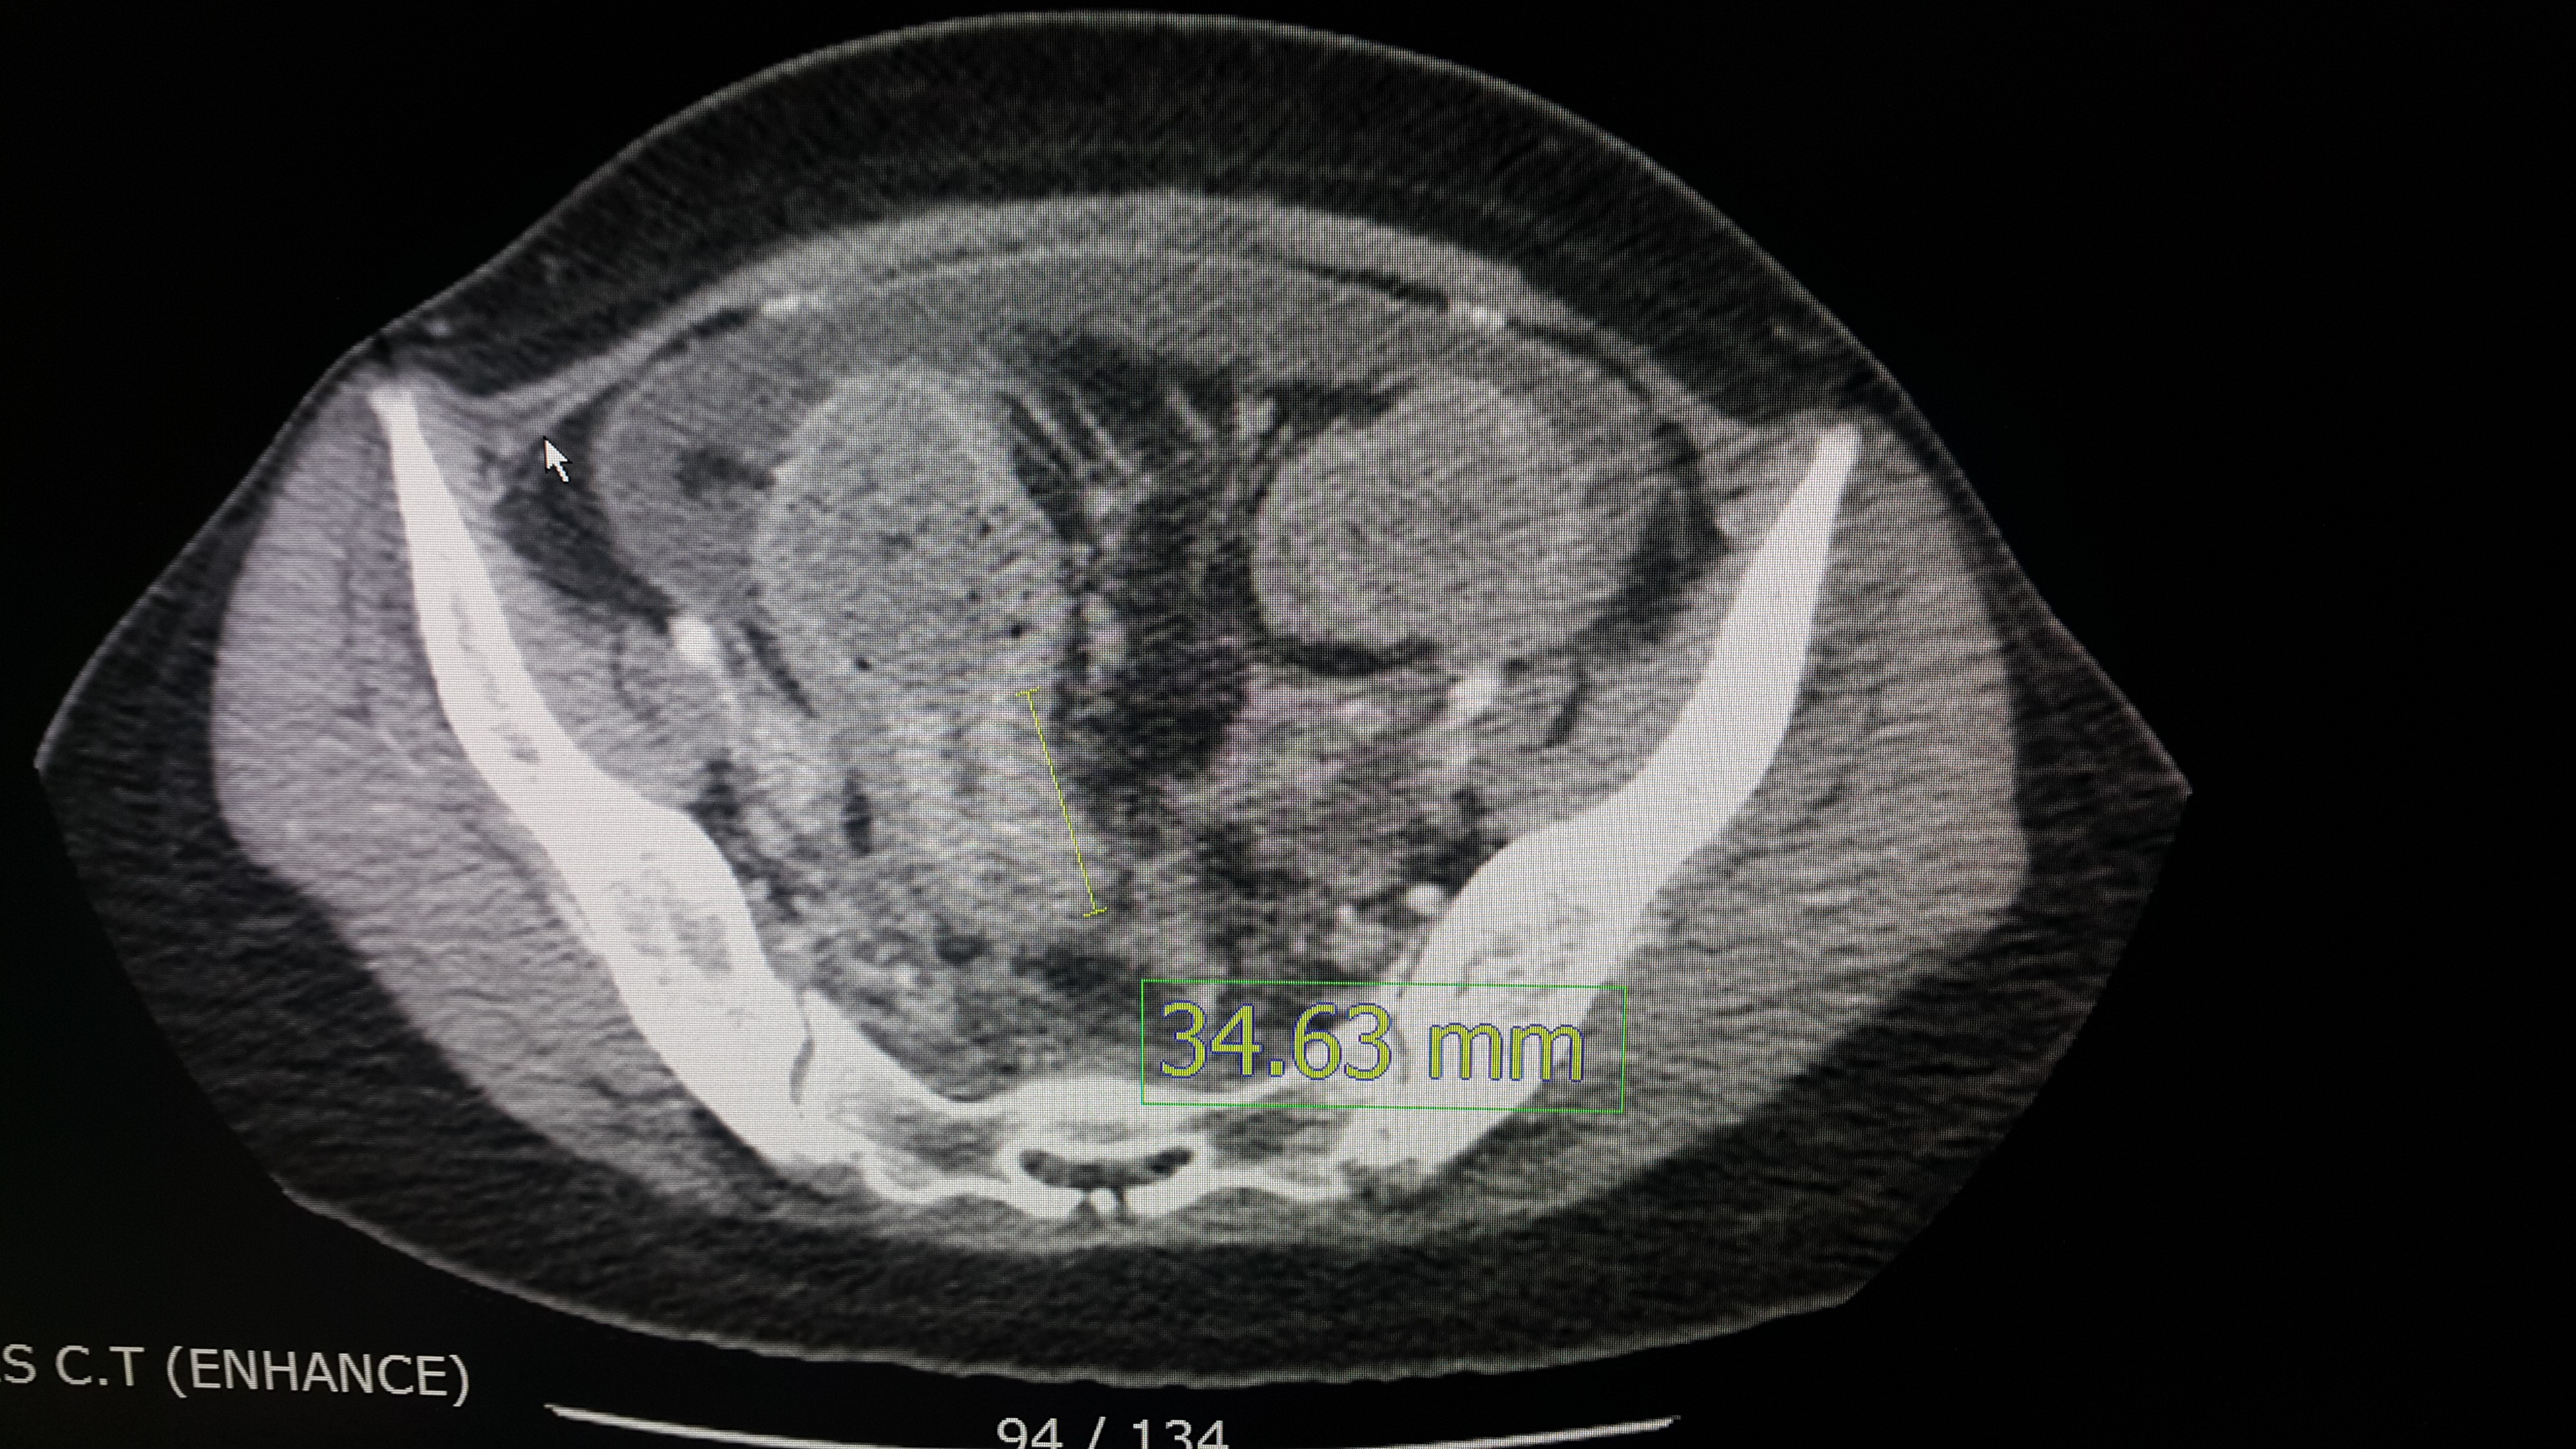

하지만 문제는 왜 대장이 막혔냐는 것이다. 다음 사진을 한 번 보자.

이것은 영상의학과에서 확인한 병변이다. (사실 나는 CT 를 봐도 어디가 병변인지 모르겠다. 역시 전문가는 다르다 ㅎㅎ) 저곳이 대장을 막고 있는 범인으로 추정된다. 하지만 여기서 문제가 되는 것은 저 병변이 (암인 것은 충분히 의심할 수 있는데) 어느 조직에서 유래한 암이냐가 치료의 방향을 결정하는 중요한 문제다. 하지만 안타깝게 CT 로는 진단이 어렵고 확진을 내리려면 조직검사를 해야하는 상황이다.